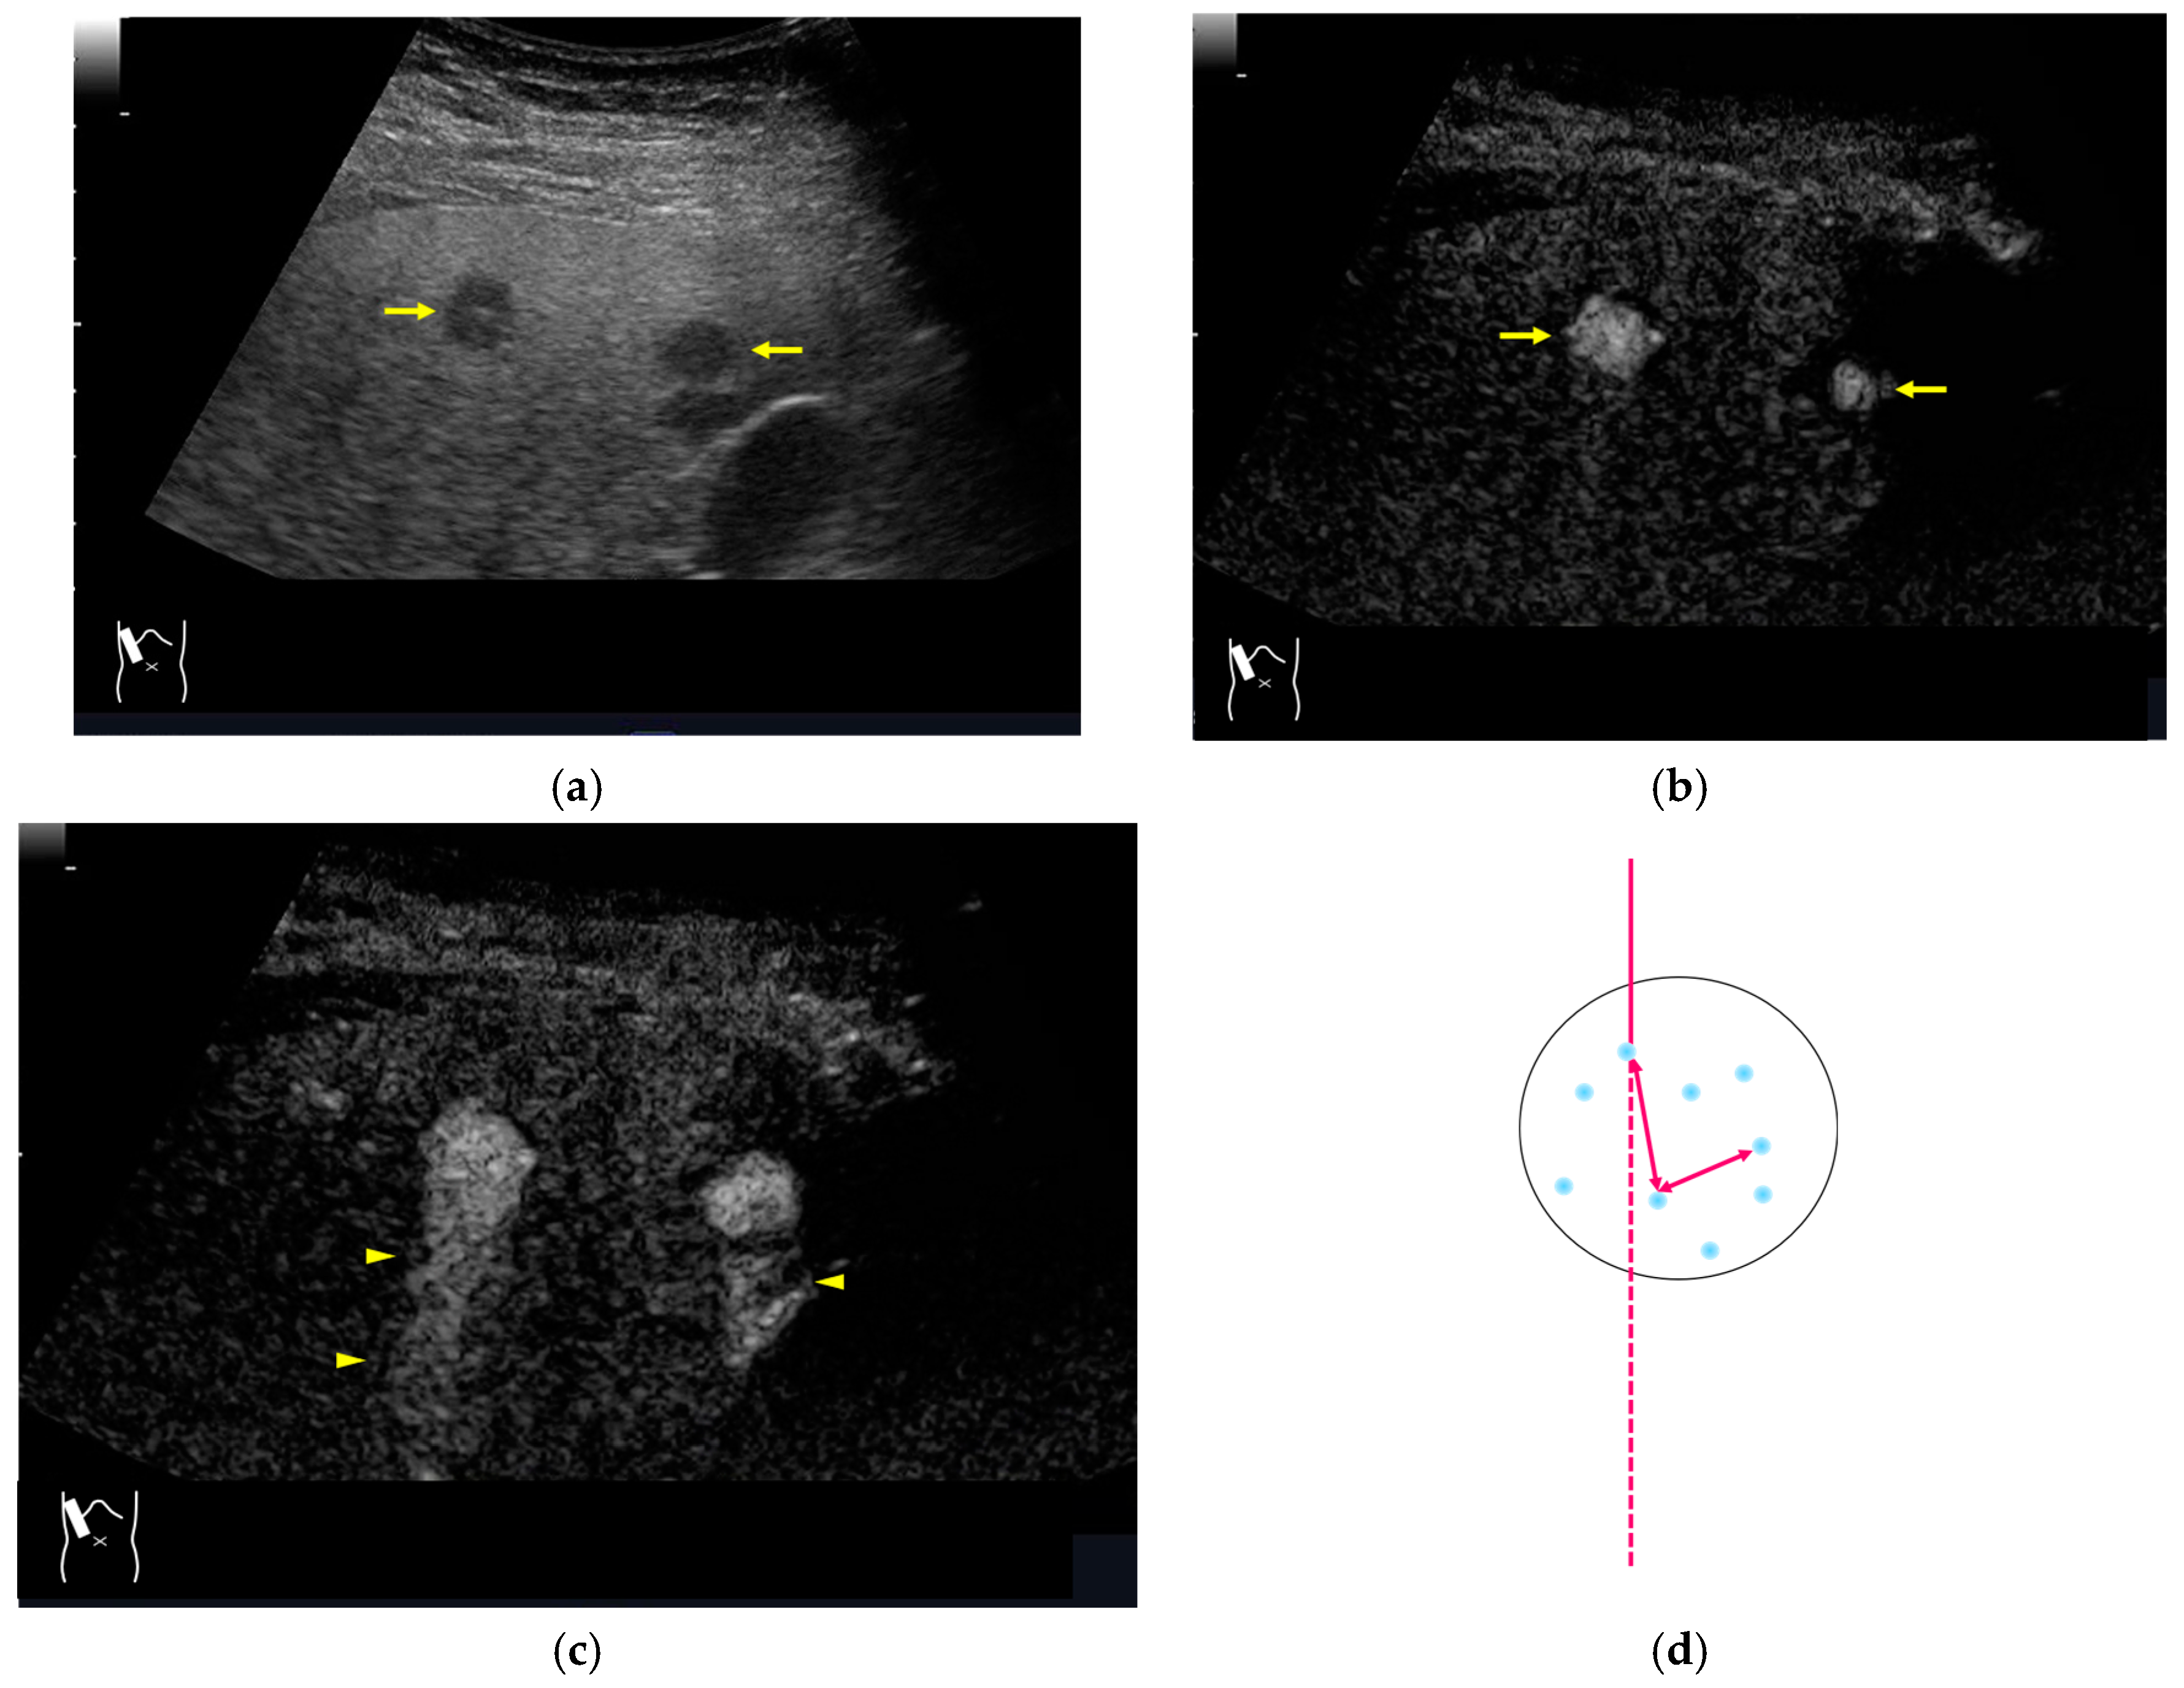

Figure 12.

Manhole-like defect in hemangioma: (a) gray-scale US of the case (arrows: hemangioma); (b) CEUS shows a cotton wool appearance in the periphery of the lesion (arrows): (c) the lesion shows a complete defect in the lesion during observation (arrows); (d) a reasonable explanation of this phenomenon. In hemangioma, destroyed microbubbles are not quickly replaced because of the low blood flow velocity, mimicking a wash-out phenomenon.

CEUS-related posterior echo enhancement (PEE) differs from that of B-mode US. PEE is the most easily recognizable US artifact, and it is characterized by an echogenic band behind a lesion with sonographically different characteristics. In B-mode US, PEE is thought to be secondary to changes in the attenuation of US beams. The area distal to a less attenuating lesion exhibits an increased US intensity and is brighter than it would be without the lesion [60,61]. Posterior echoes are also considered to be strongly related to sound refraction, which occurs when the US beam strikes the interface between two media with different acoustic velocities at an oblique angle of incidence [62]. Whether the US beams converge or diverge depends on the form of the interface and whether the sound path is from a high-velocity medium to a lower-velocity medium or the opposite. The latter condition is thought to give rise to PEE. Aside from these well-known causal factors, there are many other factors contributing to PEE, including reverberation. In brief, PEE remains a multifaced entity featuring complex interplay among sound attenuation, sound refraction, sound reverberation, and other factors. In the clinical setting, hemangioma [63], hepatocellular carcinoma [61], and hepatic cysts are known to cause PEE. We sometimes encounter CEUS-related PEE in daily CEUS examinations. It is characterized by the sudden appearance of a highly echoic zone during CEUS at a location where there was no highly echoic zone in B-mode US (Figure 14). Although this phenomenon’s mechanism of appearance has not been fully elucidated, the most plausible explanation is that many scattered signals emitted from the contrast agent, which rapidly flow into the lesion, interfere with each other inside the stained area, and the reflected time-delayed signals return to the transducer with a certain delay, resulting in the appearance of a highly echoic zone behind the lesion. The precise mechanism of CEUS-related PEE is a problem to be resolved in the near future.

Figure 14.

Posterior echo enhancement appearing during CEUS. (a) Gray-scale US of the case (arrows). (b) CEUS image of the lesion (focal nodular hyperplasia) (arrows). (c) CEUS image of posterior enhancement (arrow heads). Posterior echo enhancement appears immediately after the mass is rapidly and homogeneously enhanced. (d) Reasonable explanation of this phenomenon. Many scattered signals emitted from the bubbles that rapidly enter the mass lesion interfere with each other inside the stained area, and these scattered signals return to the transducer with a certain time-delay. These time-delayed signals are displayed as a PEE. Black circle: mass lesion; small blue circles: CEUS bubbles; red solid line: ultrasound beam; red dashed line: ultrasound is expected to travel; red arrows: reflection between bubbles.